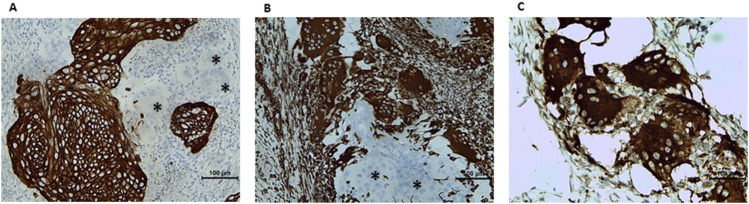

Case description: Two consecutive liquid-based cytology revealed high-grade squamous intraepithelial lesion (HSIL). Molecular testing detected HPV 18. Colposcopic findings strongly supported the clinical diagnosis of HSIL/suspicious for invasion. Histopathological examination of biopsy samples revealed typical keratinizing-type cervical SCC morphology. The patient subsequently underwent LEEP (loop electrosurgical excision procedure). Microscopic examination of resection specimen confirmed the previous diagnosis. Moreover, groups of large multinucleated cells were observed at the periphery of some invasive nests. Most of them presented the morphology of osteoclasts, whereas some giant cells were similar to Langhans cells. All the giant cells were positive for vimentin and CD68, negative for pancytokeratin. Owing to positive margins following the LEEP procedure, the patient underwent hysterectomy via the Wertheim technique. No adjuvant treatment was applied, and after the 9-month follow-up, the patient was alive with no recurrence.